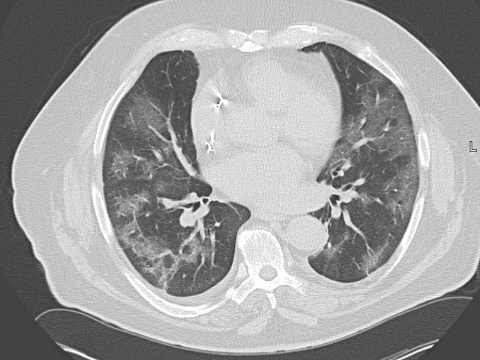

Exemplarische CT-Bildmuster des Krankheitsverlaufes einer COVID-19-Pneumonie

Die schnell fortschreitende Entwicklung der Pandemie durch die Infektion mit dem neuartigen Coronavirus (corona-virus-disease, COVID-19) hat in Deutschland zu einem rasch zunehmenden Patientenaufkommen geführt. In diesem Kontext kommt es seit Beginn der Pandemie auch immer häufiger zu computertomografischen (CT) Untersuchungen von symptomatischen Verdachtsfällen und gesicherten Infektionen mit dem „severe acute respiratory syndrome coronavirus 2“ (SARS-CoV-2).